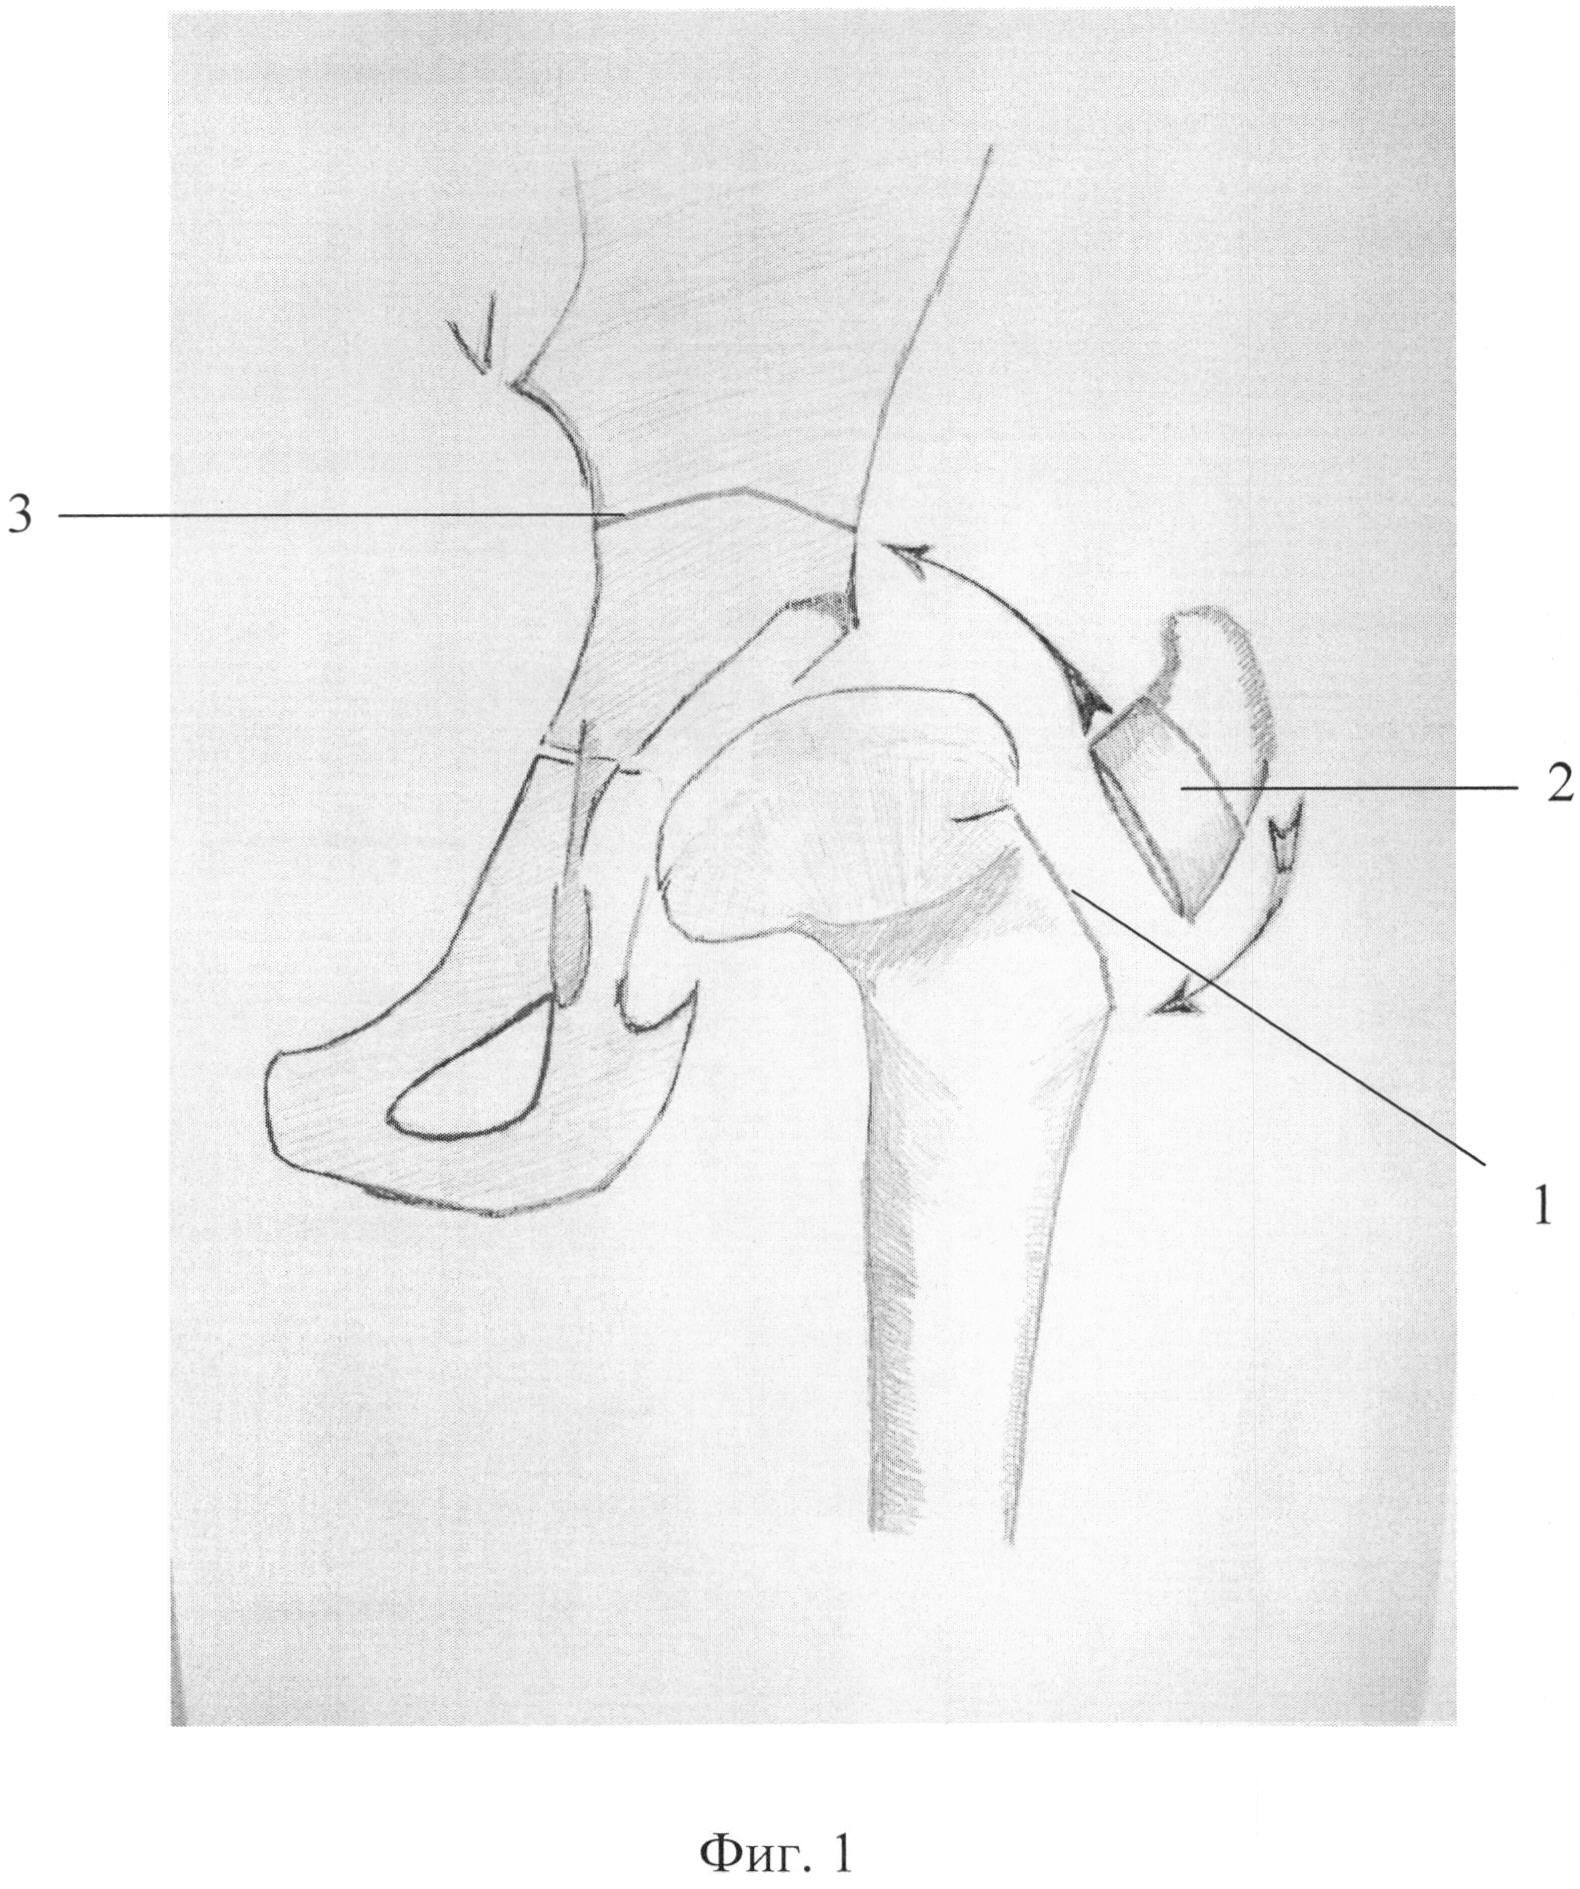

Рисунки Суставов: Анатомические Иллюстрации